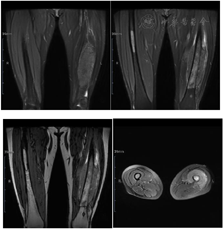

入院前查下肢彩超示:左股骨中下段骨皮质浅方实性占位。入院后查左股骨全长正侧位片示:左股骨中段骨质密度稍显减低,骨皮质毛糙、变薄,周围软组织肿胀,关节对应关系良好。查肌骨超声所见图1:左侧股骨中下段骨长轴纵切面骨皮质局部骨膜增厚,不规则隆起,可探及范围约157 mm×17 mm混合回声区,后方回声减低,交界处的骨膜回声增强、增厚、抬高呈"Codman"三角征;围绕骨干横切面见"轮辐样"放射状分布的针状强回声,回声与骨皮质表面垂直;彩超多普勒血流显像(color Doppler flow imaging,CDFI):内可探及星点状血流信号;后方骨皮质尚连续,中下段边缘毛糙。进一步查左股骨中下段增强CT所见图2:左股骨中下段髓腔内见纵形软组织密度影,邻近骨皮质稍增厚且骨质密度减低,呈筛孔样骨质破坏,周围可见放射状骨膜反应及软组织肿块,骨干未见明显膨胀,增强扫描后髓腔内见穿行血管影,周围软组织肿块中度强化。查左股骨中下段核磁见图3:左股骨干中下段髓腔内条带状长T1、压脂长T2信号影,骨皮质厚薄不均,信号欠连续,压脂信号增高,骨干周围包绕软组织块,呈略短T1、压脂长T2信号影,压脂T2其内见多发细线样低信号影垂直于骨皮质分布,病变与周围软组织区界限不清,软组织内片状长T1、压脂长T2信号影;扫描所示左股骨干远端小圆形、右股骨干中段髓腔内条带状长1、压脂长T2信号影,境界较清晰,邻近骨皮质未见明确异常。查胸部CT见图4:双肺纹理增重,双肺见多发大小不等结节样高密度影,较大者边缘欠光整,呈浅分叶状,左肺下叶见索条影,纵隔内见多发小淋巴结影;肝右叶内见类圆形低密度影,边缘可见模糊稍高密度影。腹部超声所见:肝脏实质回声致密,内可见多个低回声区,较大者大小约20 mm×14 mm的肿物;脂肪肝。查腹部ECT见肝右叶上述改变外,未见其他异常。实验室化验肿瘤标志物CEA、AFP、CA-199等都在正常范围;C反应蛋白11.43 mg/L(参考范围0.00~0.60 mg/L,以下同);碱性磷酸酶183 U/L(40~150 U/L);磷酸肌酸激酶同工酶110 U/L(1~24 U/L)。